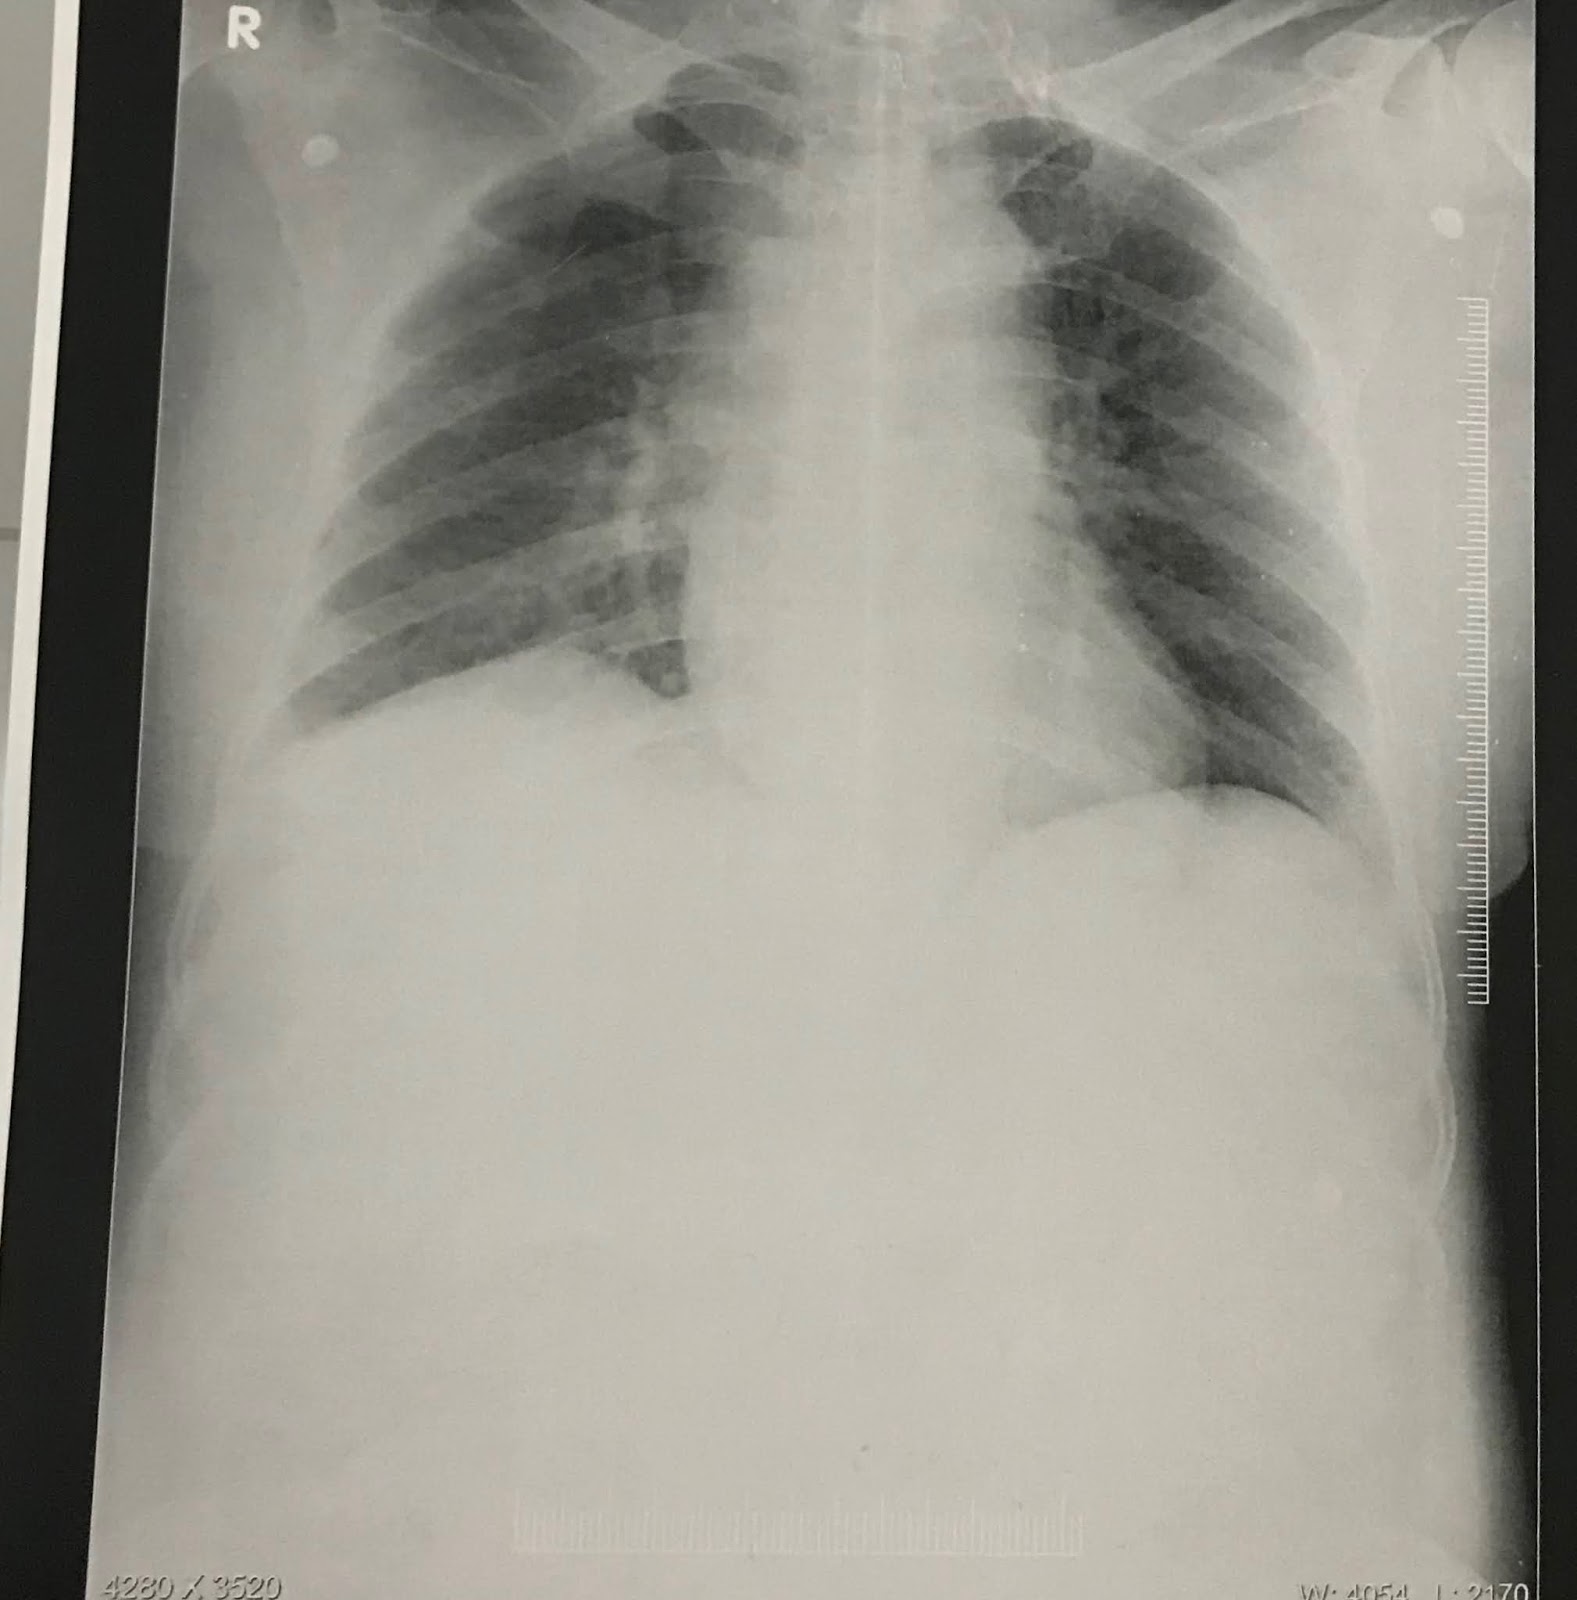

RS : BAE + , NVBS

Expiratory wheez is present at- B/L supra scapular and infra clavicular area

End expiratory crepts- B/L infra scapular and infra axillary area